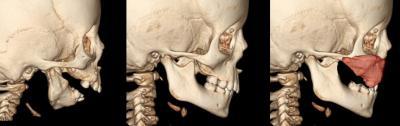

This is a 3-D CT scan of child with ACS.Pictured is a lower jaw is small and malformed (left); same-aged child with normal jaw (middle); lower jaw of child with ACS inverted over upper jaw of normal skull (right).

(Photo Credit: Seattle Children's Research Institute)